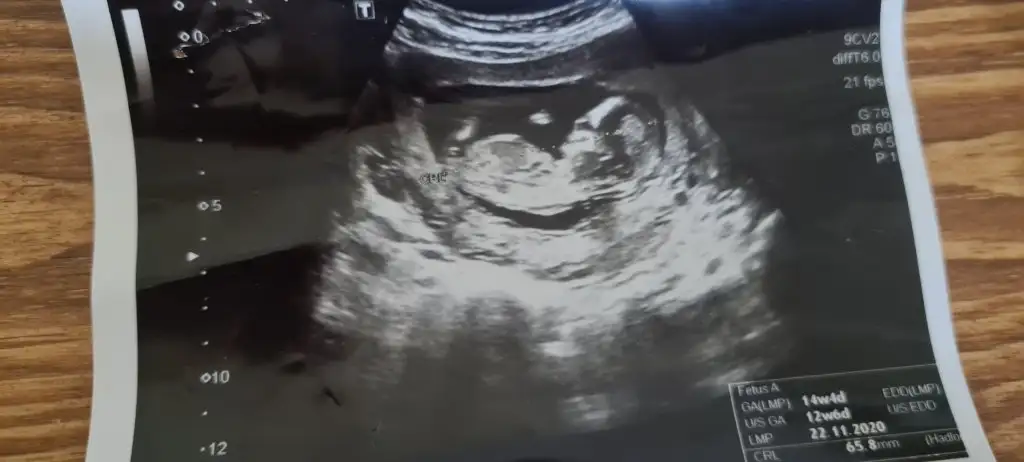

Ikra meyra Ikra meyra mrblar 13 haftalık usg attım kız demiştin canım 14+3 karından bunu da Degerlndirr msn

Eklentiler

• IMG_20210325_114624.webp

IMG_20210325_114624.webp

11,4 KB · Görüntüleme: 60

• IMG_20210325_114547.webp

IMG_20210325_114547.webp

14,1 KB · Görüntüleme: 54